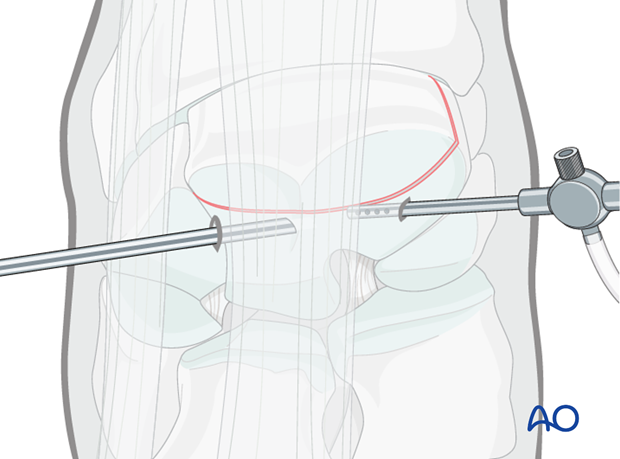

Lag screw insertion is routinely done under arthroscopic control.

This procedure is performed with the patient placed in either lateral recumbency or dorsal recumbency, through the arthroscopic approach.

In acute fractures there is frequently marked hemarthrosis and lavage will be necessary to permit visibility. This is performed by placing an egress cannula through the medial instrument portal.